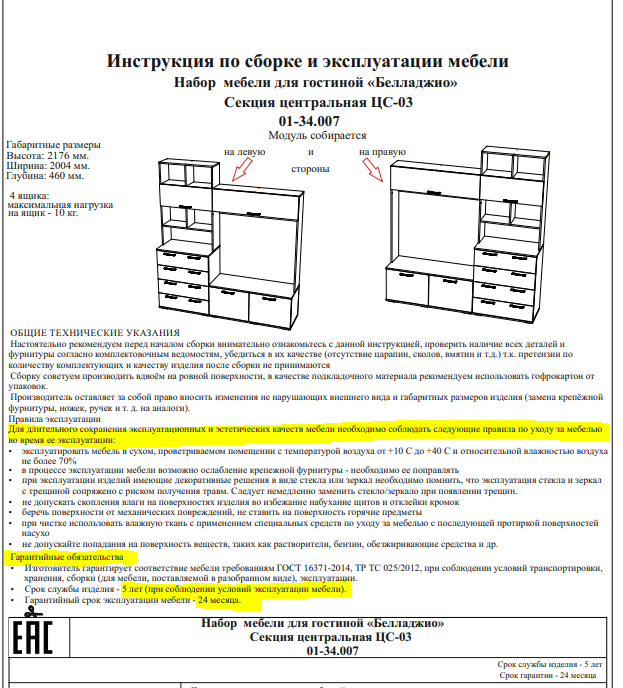

Это пациентка уютной Клиники ИН. Я установил имплантаты Xive одиннадцать лет назад, когда работал в «канАдской стоматологии». Там же её протезировали. По неизвестной науке причине, врач-ортопед выбрал, мягко говоря, неоднозначное протетическое решение — на каждый из тринадцати имплантатов был изготовлен индивидуальный абатмент, а сами зубные протезы были приклеены к ним специальным цементом. Так делать нельзя (объяснение здесь>>). Если бы сейчас кто-то из моих докторов сделал что-то подобное — вмиг погнали бы из клиники ссаными тряпками. С другой стороны, врач-ортопед (он же главный врач «канАдской» на тот момент) в миру известен как жадина и барыга — это вполне может быть причиной выбора цементной фиксации и индивидуальных абатментов там, где этого делать нельзя. К сожалению, иногда бабло побеждает добро.

Но главной проблемой подобного протетического решения является отнюдь не цена. Цементная фиксация не позволяет добраться до имплантатов в случае необходимости, поэтому любая проблема, будь то периимплантит или просто скопившийся зубной камень — это уничтожение существующего протеза и повторное протезирование со всеми вытекающими. Поэтому каждый раз, когда пациентка приходила на профилактический осмотр, я ждал контрольный снимок с замиранием сердца — очень уж переживал, что придется всё переделывать.

К счастью Елена (так зовут пациентку) оказалась очень ответственной: каждый год она приходит в нашу уютную Клинику ИН, мы делаем контрольные снимки, проводим профессиональную гигиену полости рта, которую она в течение года поддерживает гигиеной индивидуальной. Она помнит, чего стоило проведенное лечение как по финансам, так и с точки зрения нагрузки на её хрупкий женский организм, потому никогда не пропускает профилактические осмотры.

Собственно, я не зря выбрал в качестве примера столь нетривиальный и даже спорный клинический случай. Он наглядно демонстрирует, что выполнение пациентом рекомендаций по уходу и профилактическим осмотрам обеспечивают длительный срок службы имплантатов даже тогда, когда протетическая конструкция этого, вроде как, не предполагает. Иными словами, «несмотря на все усилия врачей, пациент остался жив» — и продолжает жить полной жизнью, посещая уютную Клинику ИН раз всего раз в год.